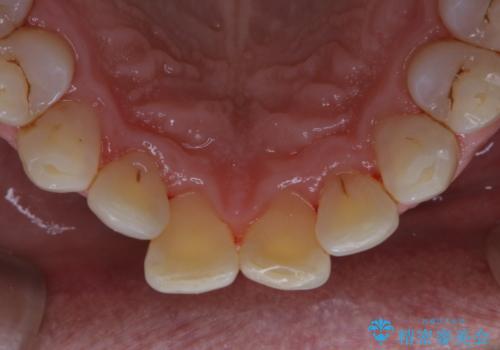

- インビザラインでの矯正治療中の方です。コーヒーをよく飲むため、着色が気になるとのことでした。PMTC60分コースを行いました。

PMTC(保険外治療)は、毎日の歯磨きで落としきれない汚れや、コーヒ、紅茶・タバコのヤニなどの着色も除去します。目には見えない歯と歯の間・歯肉の境目・インビザライン中はアタッチメント周囲などに残っているプラーク(歯垢)もしっかり取り除きます。PMTCでは専門的な機械や材料を使用して、徹底的に汚れを除去するため、虫歯・歯周病・口臭予防などにつながります。

また、仕上げのトリートメントでは歯の表面の凸凹にミネラルを補給して、ツルツルの表面に仕上げます。定期的にPMTCを行うことにより、歯質の強化になり着色がつきにくい状態になります。